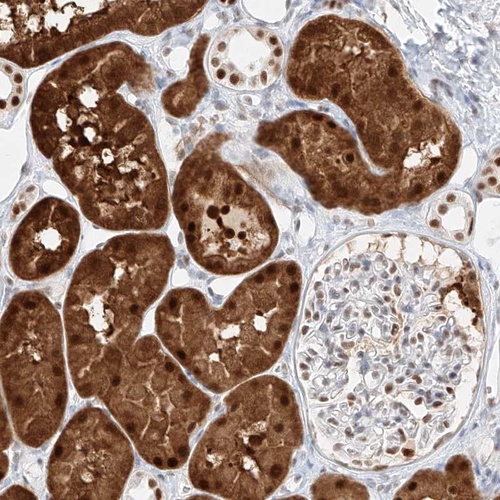

Immunohistochemical staining of human kidney shows cytoplasmic and nuclear positivity in tubular cells.